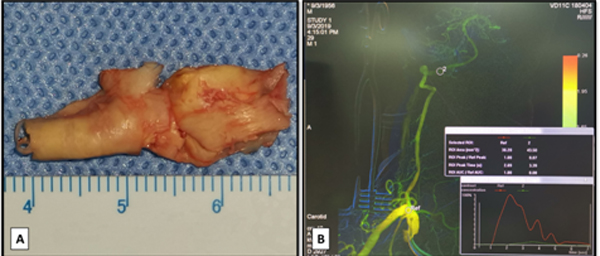

图3 A椎动脉起始部内膜斑块;B 术后即刻脑血管造影显示右侧椎动脉通畅良好

在麻醉科和手术室同道的共同努力下,右侧椎动脉闭塞复合手术血运重建手术如期进行,尽管术中发现闭塞部位斑块质地较硬,位置较深在,王东海教授还是凭借精湛的技艺熟练地将椎动脉起始部内膜斑块完整剥下(图三A),但是手术中未见到颅内明显的返向血流,术中脑血管造影证实椎动脉未通。复合手术的优势在于一期解决开刀和介入所遇到的问题,借助于复合手术室的治疗平台,治疗小组经过努力找到了椎动脉真腔,将微导管(Echelon-10,EV3,美国)输送闭塞远端,并于闭塞阶段内桥接两枚支架(APOLLO,微创,中国),造影见椎动脉通畅(图三B),术中TCD监测显示右椎动脉及双侧大脑后动脉开放良好,前后循环较术前明显改善,但无明显过度灌注。术后复查头颈部血管CTA,见右侧椎动脉开放良好,后循环血管显影良好。